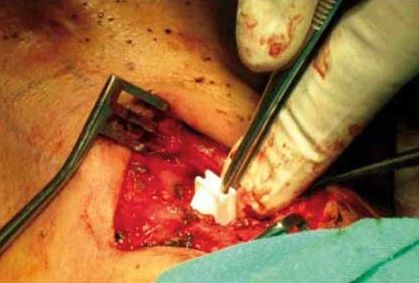

El procedimiento se lleva a cabo mediante abordaje cervical anterior. Una vez realizada la incisión se separan el platisma así como los músculos omohioideo y esternohioideo, a continuación se secciona el músculo esternotiroideo para exponer el tubérculo tiroideo en el reborde inferior del cartílago tiroides y se realiza una pequeña ventana laríngea en el mismo, retirando el fragmento de cartílago. Posteriormente, se procede a la colocación y prueba de los diferentes probadores de ventana (dispositivos de igual tamaño y forma que las prótesis definitivas), pidiéndose al paciente que hable en cada prueba y verificándose de forma simultánea la calidad de la voz y el grado de medialización de la cuerda vocal paralizada.

Aquella medida de probador ventana que mejores resultados proporcione será la seleccionada, procediéndose a la colocación de la prótesis definitiva2.